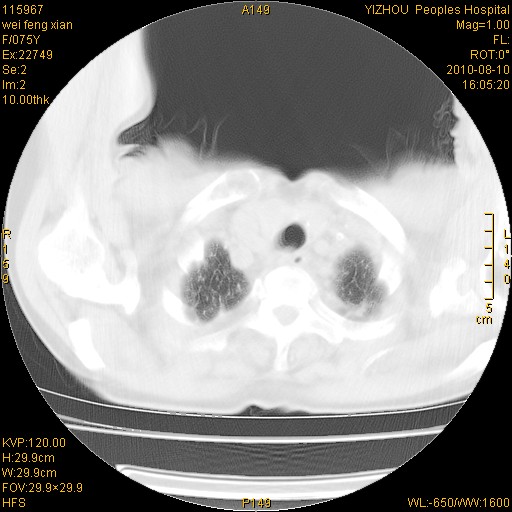

标题: CT28313:两肺弥漫性病变 [打印本页]

标题: CT28313:两肺弥漫性病变

女,75岁,患者反复头昏乏力面色苍白3年,再发10天入院。临床贫血查因。

双肺间质增生并右肺上叶炎性改变,不除外右肺上叶结核病肺内播散

双肺结核可能性大

考虑尘肺并结核;右上肺支气管扩张!

右肺上叶继发性肺结核伴肺内血型播散!

考虑右肺上叶继发性肺结核伴两肺播散。